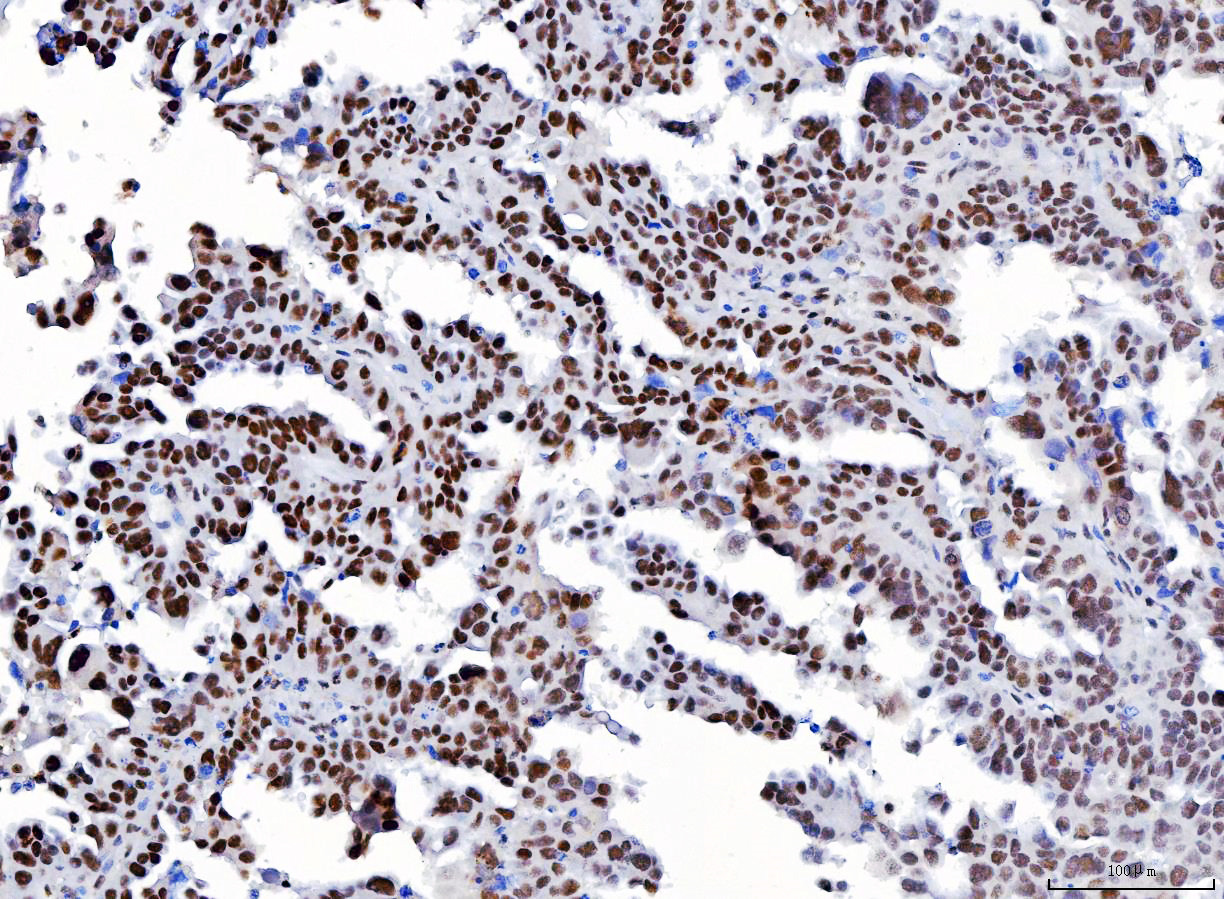

IHC analysis of YY1 using anti-YY1 antibody (M00833-3).

YY1 was detected in a paraffin-embedded section of human Laryngeal squamous cell carcinomas tissue. Biotinylated goat anti-mouse IgG was used as secondary antibody. The tissue section was incubated with mouse anti-YY1 Antibody (M00833-3) at a dilution of 1:200 and developed using Strepavidin-Biotin-Complex (SABC) (Catalog # SA1021) with DAB (Catalog # AR1027) as the chromogen.